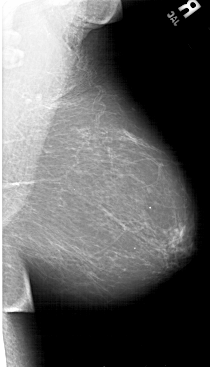

A_1492_1.RIGHT_MLO

RIGHT_MLO LINES 6601 PIXELS_PER_LINE 3766 BITS_PER_PIXEL 12 RESOLUTION 43.5 NON_OVERLAY